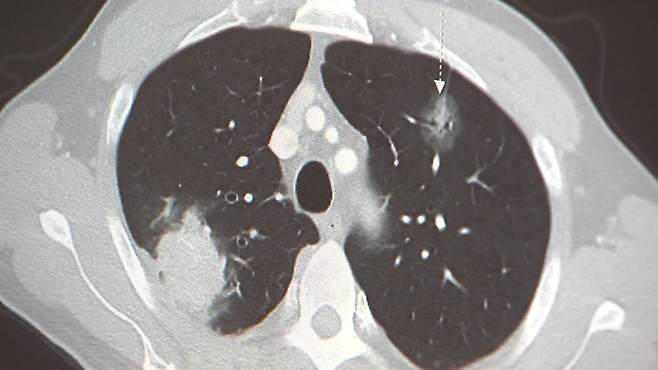

실제로 폐암을 처음 진단받은 환자들이 더 나은 치료를 찾아 여러 병원을 돌아다니는, 이른바 과도한 '닥터쇼핑'(병원 순례)이 오히려 생존율을 낮춘다는 대규모 연구 결과가 나왔습니다.

가천대 의대 연구팀이 2009년부터 2021년까지 국내 폐암 환자 28만 명을 분석한 결과, 진단 후 첫 치료까지 병원을 10회 이상 방문한 환자는 0~1회만 방문한 환자와 비교해 5년 생존율이 12% 감소한 것으로 나타났습니다.

문종윤 가천의대 예방의학과 교수는 "암 사망 1위 폐암의 경우 초기 치료가 중요한데 폐암 치료의 골든타임을 놓칠 수 있기 때문에 건강 결과를 악화시킨다"고 설명했습니다.

이소영 가천대길병원 흉부외과 교수는 "보통 미국은 6주, 우리나라는 한 달 이내에 치료를 시작할 것을 권고하고 있다"며 "만약 폐암의 성격이 공격적인 경우 치료가 조금만 지연돼도 그사이에 급격히 병이 진행한다"고 경고했습니다.